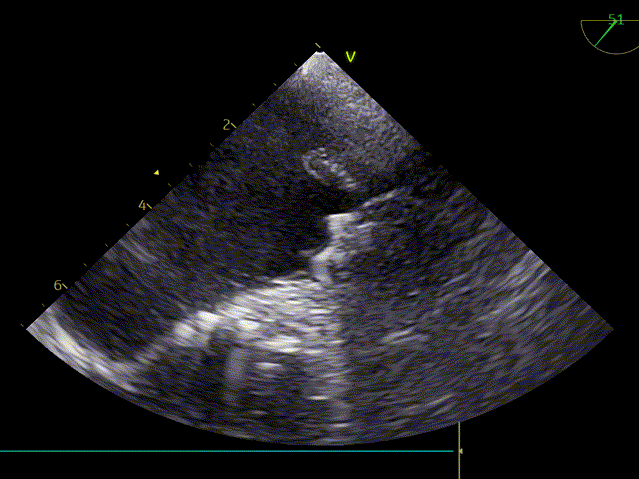

TEE45度检查左心耳

TEE0度封堵效果

TEE50度封堵效果

TEE135度封堵效果